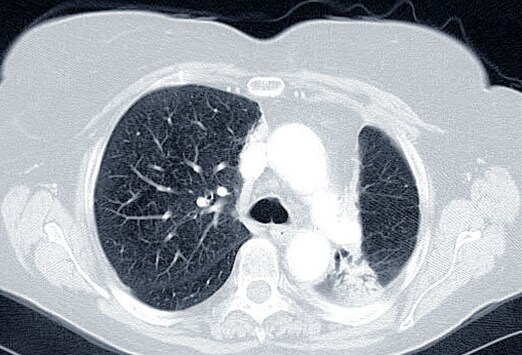

most cancers du poumon un nouveau moyen de lutter contre le. Le cancer du poumon est le plus meurtrier de tous les cancers et, depuis bien des années, les chercheurs peinent à enrayer sa progression. Mais un nouveau. Most cancers du poumon. Le cancer du poumon est la principale motive de décès par most cancers. 50% des cancers sont diagnostiqués métastatique , et seulement 20% sont localisés. Cancer du poumon, symptômes, métastase, stade et survie. Le cancer du poumon provoque l. A. Formation d'une masse tumorale maligne. Avec le temps, cette masse s'étend et provoque des troubles de l'organe ainsi que des.

Cancer du poumon, symptômes, métastase, stade et survie. Le cancer du poumon provoque la formation d'une masse tumorale maligne. Avec le temps, cette masse s'étend et provoque des troubles de l'organe ainsi que des.